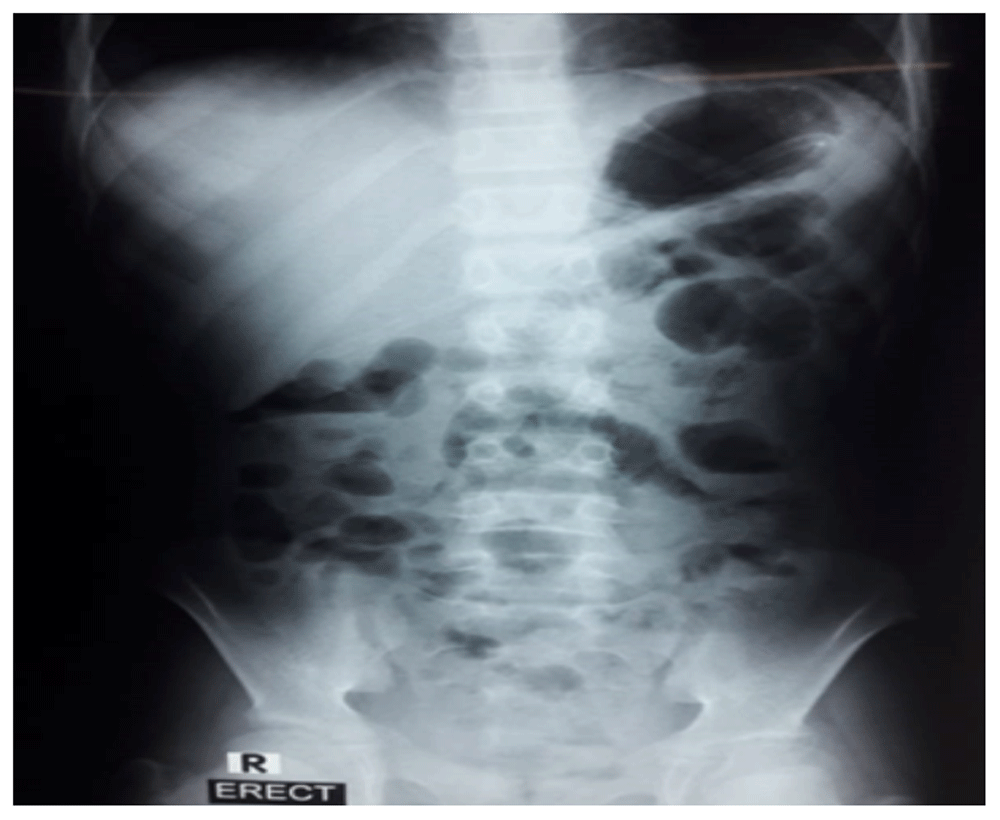

The patient passed stool and had no issues of vomiting, so she was discharged on the second day of admission after dietary counseling. X-ray abdomen showed normal gaseous shadows (Figure 3). Scheduled follow up after 10 days, showed that the patient was in good condition.

Figure 3. X-ray of the abdomen showing normal gaseous shadows after treatment.